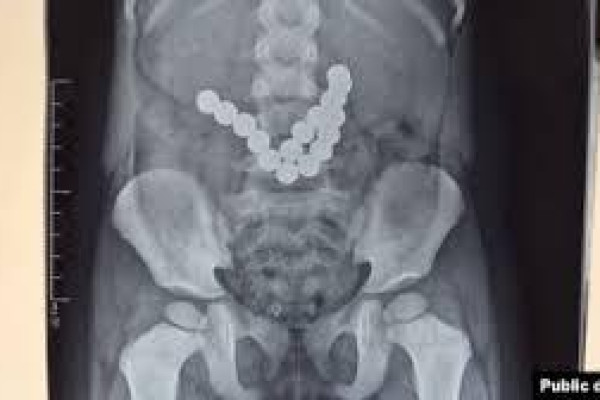

Ошто 2 жашар баланын ичегисинен 17 даана магнит чыгарылды

Ошто 17 магнитти жутуп алган эки жаштагы балага операция жасалды